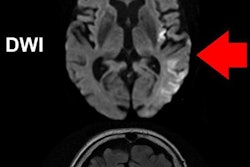

Images depict the distribution of lesions in the dataset: the redder the color, the greater the number of patients with lesions in that part of the brain. Courtesy of USC Mark and Mary Stevens Neuroimaging and Informatics Institute/Tyler Ard.Typically, researchers manually draw boundaries around stroke-related lesions. With the help of new algorithms, an automated segmentation process would be able to analyze more images.